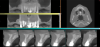

Fig 11. The CBCT and virtual wax-up plan were merged together, and virtual implant placement was done; frontal view (Fig 11), and occlusal view (Fig 12).

Fig 12. The CBCT and virtual wax-up plan were merged together, and virtual implant placement was done; frontal view (Fig 11), and occlusal view (Fig 12).

Fig 13. The teeth to be clinically extracted were now virtually extracted, leaving only the abutment teeth.

The laboratory virtually extracted teeth Nos. 6, 10, and 11 and designed the provisional restoration, copying the original bridge design (Figure 9 and Figure 10). The die spacer thickness parameter was set to cement gap 0.045 mm with an extra cement gap of 0.065 mm. This file was then imported into surgical planning and guide design software, and final implant positions were planned for the area where implants could be placed (Figure 11 through Figure 13). This plan was verified by the clinicians, and the surgical guide was designed to sit on the prepared teeth (Figure 14).